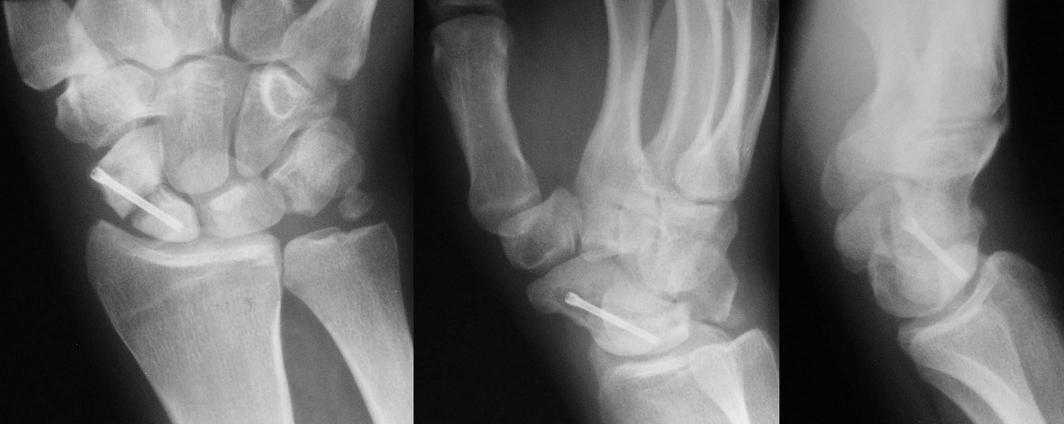

I am not sure if the differential of a nonunion vs. pseudoarthrosis means much in this context. The distal pole of the screw has a lucency, so the

nonunion is most likely unstable and moving. It needs revision. The radial styloid does not have evidence of DJD, so I do not think it needs to be resected. The surgery will probably require an open revision, removal of necrotic bone and soft tissue interposition, and would benefit from some

distal radial autograft. The patient needs to refrain from smoking and I would use a case to be sure they do not move for a while. A stiff wrist is not a bad outcome; a bad outcome is a painful wrist.

Такое ощущение, что имеющееся состояние ещё не является необратимым (отсутствие склероза отломков на уровне перелома) и обусловлено исключительно нестабильностью (сам винт оказался слабоват или чрезмерные нагрузки привели к срыву фиксации - пациент, заметьте, мотоциклист!)

Почему-то хочется верить, что можно добиться сращения, если вернуть кости стабильность путём компрессионного остеосинтеза более мощным винтом без открытого вмешательства на компрометированной зоне и защитить фиксацию строгим соблюдением режима. Я сильно ошибаюсь?

Ув. Данил! По моему мнению все-таки ложный сустав -склероз отломков (приложение), 5 мес, диастаз. Для подтверждения можно выполнить КТ кистевого сустава (формирование замыкательной пластинки, склероз концов отломков и т.д.,), а так же по КТ можно выявить сохраняется ли подвывих каких-либо костей запястья или нет. При наличии ложного сустава целесообразно будет удалить винт,обработать концы отломков, разрушив замыкательные пластинки и выполнить остеосинтез ладьевидной кости винтом с костной аутопластикой зоны псевдоартроза (либо гидроксиаппатитом...) Гипс 1,5 мес мин. Снимков найти сейчас не получилось. позже дошлю.